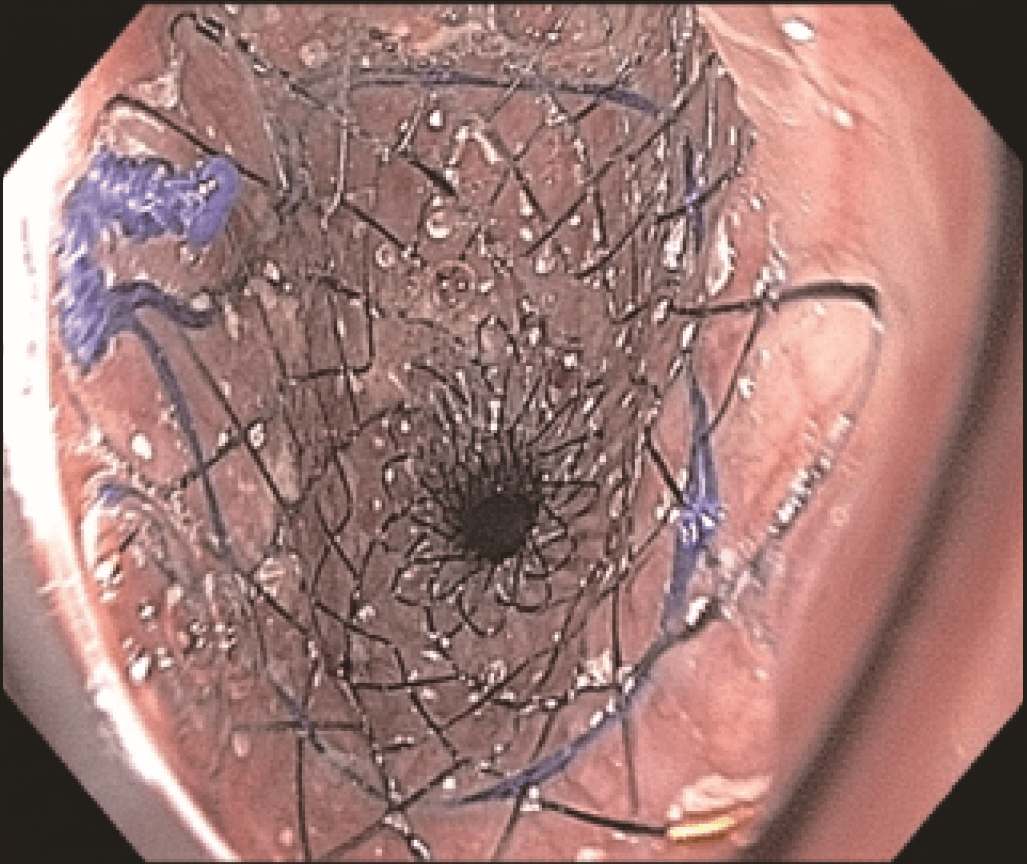

Endoscopic evaluation identified a stricture located at the proximal end of the SEMS (Figures 3 and 4) at 20 cm from the incisors, apparently caused by tumor growth. The upper esophageal sphincter was located at 16 cm from the incisors.

The stricture was located at the uncovered proximal end of the initial SEMS, placed at the cervical esophagus. The stricture was hard and did not allow the passage of the 4.9 mm scope.

However, the three marks at the HANAROSTENT’s distal, medial and proximal ends were easily seen under fluoroscopic guidance, and were valuable in ensuring acurate deployment, just distal to the upper esophageal sphincter (Figure 5). The distal end of the HANAROSTENT remained in the patent portion of the previous stent. The endoscopic view of the SEMS proximal end can be observed in the images below (Figures 6, 7 and 8).